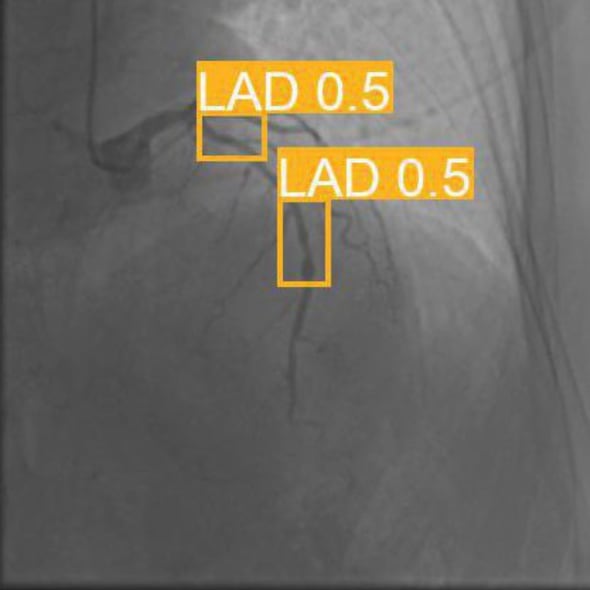

A research project developing a hybrid LSTM-CNN deep-learning model for the automated detection and classification of coronary artery stenoses from angiographic images. The system combines convolutional neural networks for spatial feature extraction with long short-term memory networks for sequential analysis of angiographic sequences, achieving accurate stenosis grading.

Hybrid LSTM-CNN Coronary Stenosis Detection 2023

AI and Smart EnvironmentLessage X, Nedoszytko M, Mahmoudi S, Marey L, Debauche O

Deep CNN for Coronary Artery Classification 2020

Int J Computer Assisted Radiology and SurgeryLessage X, Nedoszytko M, Mahmoudi SA, Mahmoudi S, Piussi C